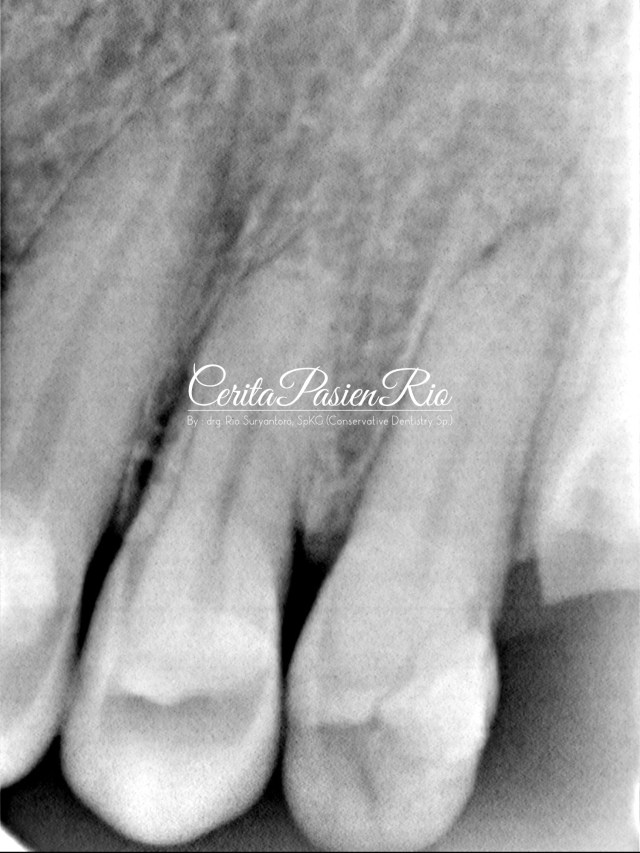

kemudian, saya lakukan foto rontgent dengan keadaan seperti dibawah ini.

gambar 3. foto rontgent dental menunjukkan adanya kehilangan jaringan gigi yang cukup banyak dimulai dari bagian proksimal distal.